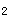

男孩,2歲,雙眼疼痛1年,右側(cè)眼球突出。CT平掃如圖:

正確答案:3.A;4.D 解題思路:視網(wǎng)膜母細(xì)胞瘤是兒童眼球內(nèi)最常見的惡性腫瘤,多見于3歲以下的幼兒,多數(shù)為單眼發(fā)病,約1/4的病人雙眼發(fā)病,CT表現(xiàn)為眼球內(nèi)實(shí)性腫塊,若伴有斑塊或斑點(diǎn)狀鈣化則較具特征。腫瘤較大致眼球增大、突出。視網(wǎng)膜母細(xì)胞瘤為起源于視網(wǎng)膜的胚胎性惡性腫瘤。